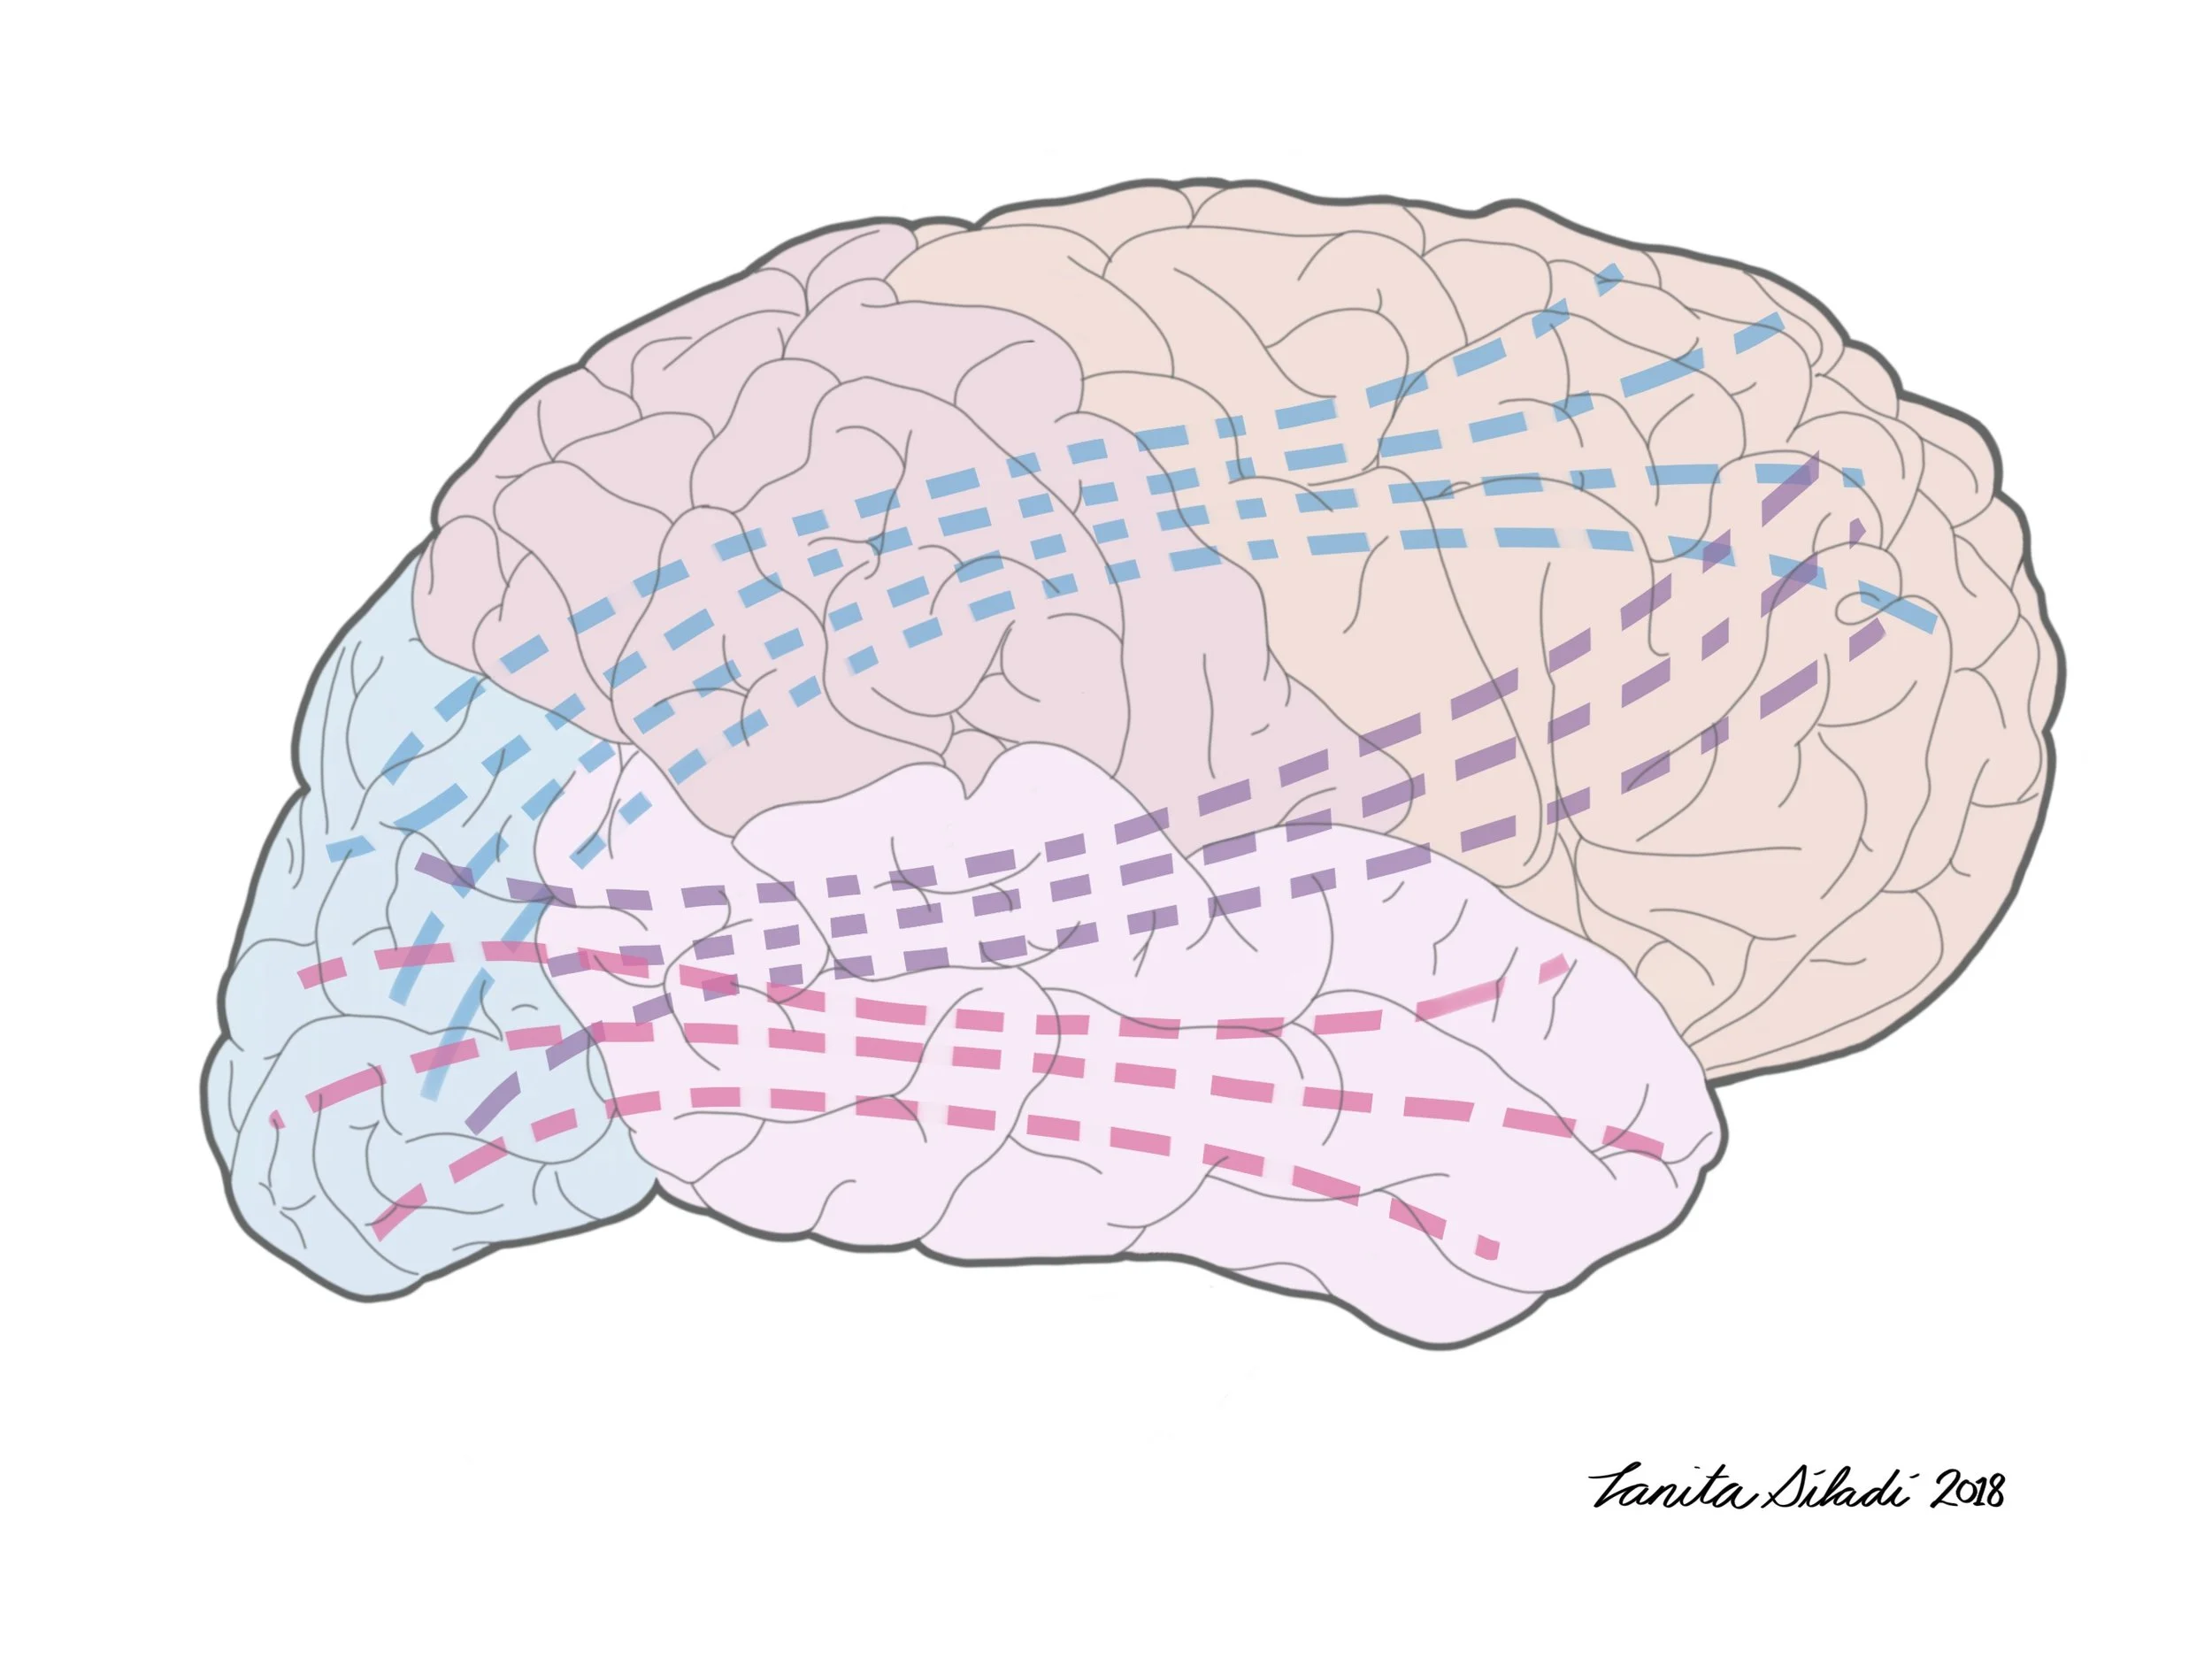

Dissertation illustration: Hurtubise, J. Behavioural effects of concussion history and their underlying neural mechanisms in elite and non-elite athletes. (July 2018)

Dissertation illustration: Hurtubise, J. Behavioural effects of concussion history and their underlying neural mechanisms in elite and non-elite athletes. (July 2018)